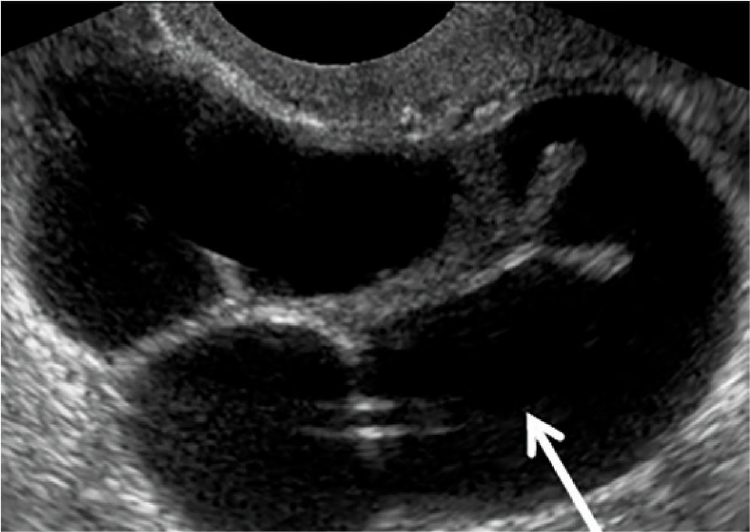

Quais sinais ultrassonográficos de DIP/

A

Espessamento tubáreo

Septos incompletos tubáreos

Sinal da roda denteada - cogwheel sign (ABAIXO)

Líquido na tuba

Abscesso tubo-ovariano

Q

O que significa o sinal da roda denteada?